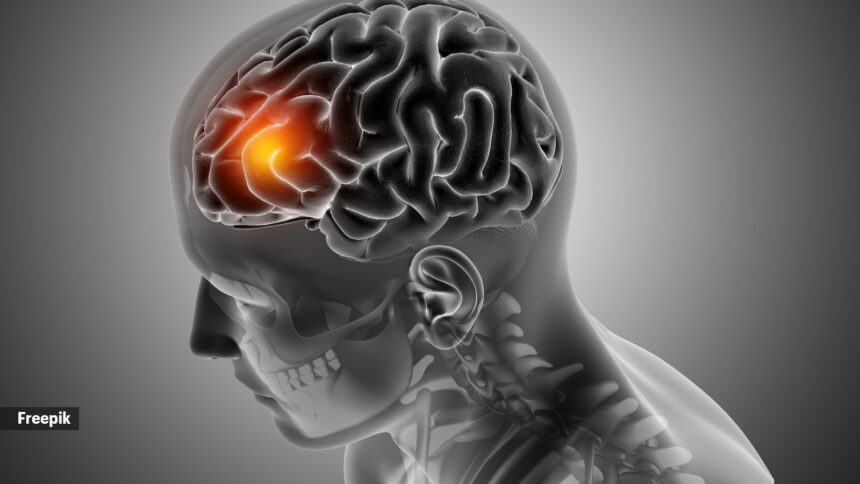

A recent study by the Indian Council of Medical Research has flagged a worrying trend: 1 in 7 stroke patients in India are aged 18–44, and nearly 2 in 5 reach hospital after 24 hours of symptom onset—delays that can severely impact recovery. The analysis covered 34,792 stroke cases registered across 30 hospitals between January 2020 and December 2022.

The study also found hypertension in nearly three-fourths of patients, making it the leading risk factor for brain stroke.